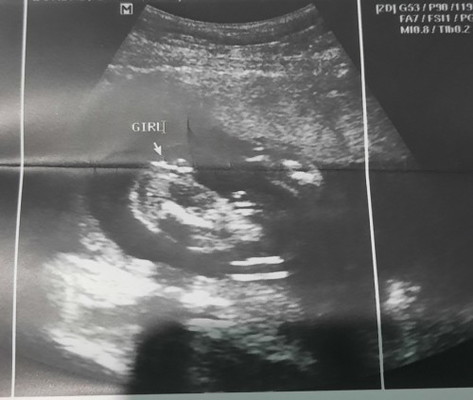

If sabi ng sono niyo na girl, most likely girl po. Mataas naman po ang percentage na tama ang nakita ng sono sa ultrasound. Malabo lang ang ink ng result pero nakita naman po nila yan bago po binigay sa inyo ang print-out.